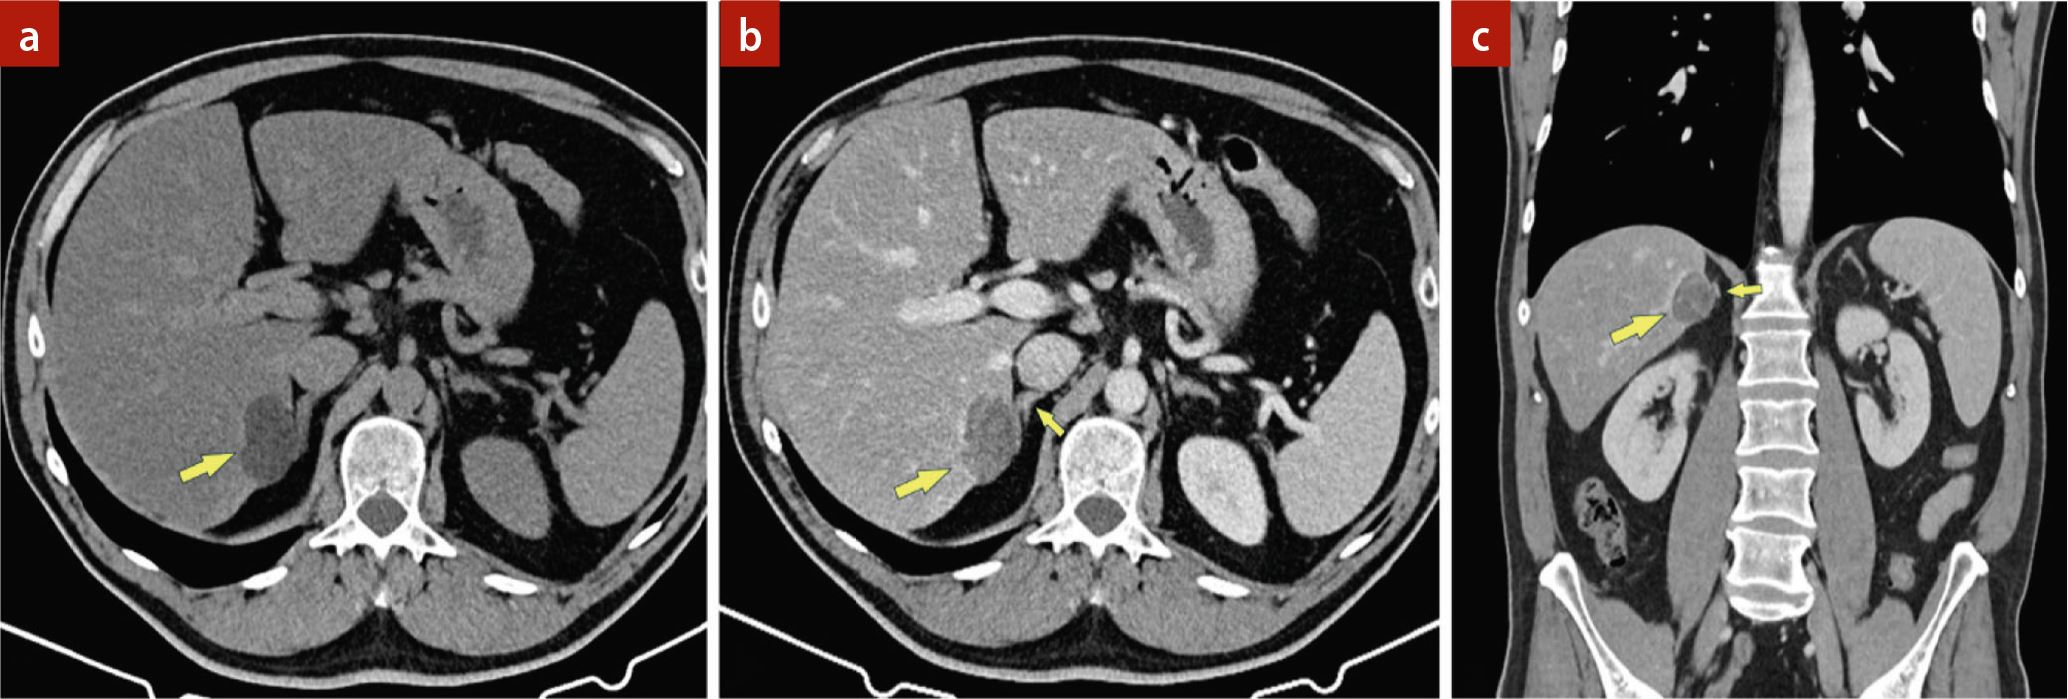

Bei einem 50-jährigen Patienten wurde auswärts in einer Sonografie eine unklare Raumforderung im rechten Leberlappen festgestellt. Der Patient wies keine Vorerkrankungen auf, keine chronische Lebererkrankung, die Leberfunktionsparameter waren im Normbereich. Es wurde daraufhin eine kontrastmittelverstärkte Multidetektor-Computertomografie (MDCT) durchgeführt, die eine ausgeprägte diffuse Steatose der Leber zeigte, mit einer 3,9 cm großen subkapsulären Raumforderung im rechten Leberlappen (S 6/7). Diese Läsion war eindeutig fett-haltig (Dichte nativ, –8 HU) und zeigte nach Kontrastmittel (KM) ein geringes Enhancement (▶Abb. 1). Zur weiteren Abklärung wurde der Patient an unsere Abteilung verwiesen, wo eine Magnetresonanztomografie (MRT) mit extrazellulärem gadoliniumhaltigem KM durchgeführt wurde. Auch in der MRT war eine ausgeprägte Verfettung des Tumors und eine KM-Aufnahme zu sehen (▶Abb. 2). Abgesehen von der diffusen Steatose der Leber fand sich kein Hinweis auf eine Lebererkrankung.

Magnetresonanztomografie (MRT) der Leber. a) Die fettsensitive Sequenz (Opposed-Phase) in der MRT zeigt einen ausgeprägten Signalabfall des Tumors (Pfeil) als Ausdruck einer massiven Verfettung. b) Nach Kontrastmittelgabe ist die Vaskularisierung der Raumforderung und die unmittelbare Nähebeziehung zur rechten Nebenniere (kleiner Pfeil) erkennbar. Im Leberparenchym gibt es keine Zirrhosezeichen.